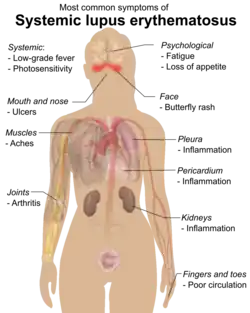

Signs and symptoms

SLE is one of several diseases known as "the great imitator" because it often mimics or is mistaken for other illnesses.[12] SLE is a classical item in differential diagnosis,[13] because SLE symptoms vary widely and come and go unpredictably. Diagnosis can thus be elusive, with some people having unexplained symptoms of SLE for years before a definitive diagnosis is reached.[14]

Common initial and chronic complaints include fever, malaise, joint pains, muscle pains, and fatigue. Because these symptoms are so often seen in association with other diseases, these signs and symptoms are not part of the diagnostic criteria for SLE. When occurring in conjunction with other signs and symptoms, however, they are considered suggestive.[15]

While SLE can occur in both males and females, it is found far more often in women, and the symptoms associated with each sex are different.[9] Females tend to have a greater number of relapses, a low white blood cell count, more arthritis, Raynaud syndrome, and psychiatric symptoms. Males tend to have more seizures, kidney disease, serositis (inflammation of tissues lining the lungs and heart), skin problems, and peripheral neuropathy.[16]

Skin

As many as 70% of people with lupus have some skin symptoms. The three main categories of lesions are chronic cutaneous (discoid) lupus, subacute cutaneous lupus, and acute cutaneous lupus. People with discoid lupus may exhibit thick, red scaly patches on the skin. Similarly, subacute cutaneous lupus manifests as red, scaly patches of skin but with distinct edges. Acute cutaneous lupus manifests as a rash. Some have the classic malar rash (commonly known as the butterfly rash) associated with the disease.[17] This rash occurs in 30–60% of people with SLE.[18]

Hair loss, mouth and nasal ulcers, and lesions on the skin are other possible manifestations.[19]

Muscles and bones

The most commonly sought medical attention is for joint pain, with the small joints of the hand and wrist usually affected, although all joints are at risk. More than 90 percent of those affected will experience joint or muscle pain at some time during the course of their illness.[20] Unlike rheumatoid arthritis, lupus arthritis is less disabling and usually does not cause severe destruction of the joints. Fewer than ten percent of people with lupus arthritis will develop deformities of the hands and feet.[20] People with SLE are at particular risk of developing osteoarticular tuberculosis.[21]

A possible association between rheumatoid arthritis and SLE has been suggested,[22] and SLE may be associated with an increased risk of bone fractures in relatively young women.[23]

Blood

Anemia is common in children with SLE[24] and develops in about 50% of cases.[25] Low platelet count (thrombocytopenia) and low white blood cell count (leukopenia) may be due to the disease or a side effect of pharmacological treatment. People with SLE may have an association with antiphospholipid antibody syndrome[26] (a thrombotic disorder), wherein autoantibodies to phospholipids are present in their serum. Abnormalities associated with antiphospholipid antibody syndrome include a paradoxical prolonged partial thromboplastin time (which usually occurs in hemorrhagic disorders) and a positive test for antiphospholipid antibodies; the combination of such findings have earned the term "lupus anticoagulant-positive". Another autoantibody finding in SLE is the anti-cardiolipin antibody, which can cause a false positive test for syphilis.[27]

Heart

SLE may cause pericarditis (inflammation of the outer lining surrounding the heart), myocarditis (inflammation of the heart muscle), or endocarditis (inflammation of the inner lining of the heart). The endocarditis of SLE is non-infectious, and is also called Libman–Sacks endocarditis. It involves either the mitral valve or the tricuspid valve. Atherosclerosis also occurs more often and advances more rapidly than in the general population.[28][29]

Steroids are sometimes prescribed as an anti-inflammatory treatment for lupus; however, they can increase one's risk for heart disease, high cholesterol, and atherosclerosis.[30]

Lungs

SLE can cause pleuritic pain as well as inflammation of the pleurae known as pleurisy, which can rarely give rise to shrinking lung syndrome involving a reduced lung volume.[31][32] Other associated lung conditions include pneumonitis, chronic diffuse interstitial lung disease, pulmonary hypertension, pulmonary emboli, and pulmonary hemorrhage.[33][34]

Kidneys

Painless passage of blood or protein in the urine may often be the only presenting sign of kidney involvement. Acute or chronic renal impairment may develop with lupus nephritis, leading to acute or end-stage kidney failure. Because of early recognition and management of SLE with immunosuppressive drugs or corticosteroids,[35] end-stage renal failure occurs in less than 5%[36][37] of cases, except in the black population, where the risk is many times higher.

The histological hallmark of SLE is membranous glomerulonephritis with "wire loop" abnormalities.[38] This finding is due to immune complex deposition along the glomerular basement membrane, leading to a typical granular appearance in immunofluorescence testing.

Neuropsychiatric

Neuropsychiatric syndromes can result when SLE affects the central or peripheral nervous system. The American College of Rheumatology defines 19 neuropsychiatric syndromes in systemic lupus erythematosus.[39] The diagnosis of neuropsychiatric syndromes concurrent with SLE (now termed as NPSLE),[40] is one of the most difficult challenges in medicine, because it can involve so many different patterns of symptoms, some of which may be mistaken for signs of infectious disease or stroke.[41]

A common neurological disorder people with SLE have is headache,[42] although the existence of a specific lupus headache and the optimal approach to headache in SLE cases remains controversial.[43] Other common neuropsychiatric manifestations of SLE include cognitive disorder, mood disorder, cerebrovascular disease,[42] seizures, polyneuropathy,[42] anxiety disorder, psychosis, depression, and in some extreme cases, personality disorders.[44] Steroid psychosis can also occur as a result of treating the disease.[40] It can rarely present with intracranial hypertension syndrome, characterized by an elevated intracranial pressure, papilledema, and headache with occasional abducens nerve paresis, absence of a space-occupying lesion or ventricular enlargement, and normal cerebrospinal fluid chemical and hematological constituents.[45]

More rare manifestations are acute confusional state, Guillain–Barré syndrome, aseptic meningitis, autonomic disorder, demyelinating syndrome, mononeuropathy (which might manifest as mononeuritis multiplex), movement disorder (more specifically, chorea), myasthenia gravis, myelopathy, cranial neuropathy and plexopathy.[46]

Neurological disorders contribute to a significant percentage of morbidity and mortality in people with lupus.[47] As a result, the neural side of lupus is being studied in hopes of reducing morbidity and mortality rates.[39] One aspect of this disease is severe damage to the epithelial cells of the blood–brain barrier. In certain regions, depression affects up to 60% of women with SLE.[48]

Eyes

Up to one-third of patients report that their eyes are affected. The most common diseases are dry eye syndrome and secondary Sjögren's syndrome, but episcleritis, scleritis, retinopathy (more often affecting both eyes than one), ischemic optic neuropathy, retinal detachment, and secondary angle-closure glaucoma may occur. In addition, the medications used to treat SLE can cause eye disease: long-term glucocorticoid use can cause cataracts and secondary open-angle glaucoma, and long-term hydroxychloroquine treatment can cause vortex keratopathy and maculopathy.[49]

Reproductive

While most pregnancies have positive outcomes, there is a greater risk of adverse events occurring during pregnancy.[50] SLE causes an increased rate of fetal death in utero and spontaneous abortion (miscarriage). The overall live-birth rate in people with SLE has been estimated to be 72%.[51] Pregnancy outcome appears to be worse in people with SLE whose disease flares up during pregnancy.[52]

Neonatal lupus is the occurrence of SLE symptoms in an infant born from a mother with SLE, most commonly presenting with a rash resembling discoid lupus erythematosus, and sometimes with systemic abnormalities such as heart block or enlargement of the liver and spleen.[53] Neonatal lupus is usually benign and self-limited.[53]

Medications for treatment of SLE can carry severe risks for female and male reproduction. Cyclophosphamide (also known as Cytoxan), can lead to infertility by causing premature ovarian insufficiency (POI), the loss of normal function of one's ovaries prior to age forty.[54] Methotrexate can cause termination or deformity in fetuses and is a common abortifacient, and for men taking a high dose and planning to father, a discontinuation period of 6 months is recommended before insemination.[55]

Systemic

Fatigue in SLE is probably multifactorial and has been related to not only disease activity or complications such as anemia or hypothyroidism, but also to pain, depression, poor sleep quality, poor physical fitness and lack of social support.[56][57]